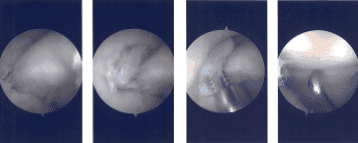

Imágenes de artroscopia intraoperatoria

Luego, el artroscopio se trasladó al compartimento lateral donde se vio un desgarro. Se realizó un portal de entrada medial con acceso directo al menisco izquierdo. Se introdujeron los instrumentos y se limpió el margen lateral del menisco medial, así como el deshilachado en el margen lateral del menisco medial, utilizando una maquinadora.

El artroscopio se introdujo en la zona intercondilar donde hubo un desgarro parcial de las fibras del LCA. El artroscopio se introdujo en el compartimento femoral lateral, donde se volvió a ver el desgarro. La tercera lágrima fue completamente desbridada con una afeitadora y un bitter puro.

Tras el desbridamiento exhaustivo del desgarro, el endoscopio se trasladó a una articulación patelofemoral donde se observaron cambios osteoartríticos de grado 3 a grado 4. La condroplastia de la superficie rotuliana posterior se realizó mediante una afeitadora.

Hubo un cambio osteoartrítico de grado 1 en la troclea. Era un cambio osteoartrítico de grado 1 a 2 en el compartimento femoral medial, cóndilo femoral medial posterior, que fue afeitado.

Ahora, el artroscopio se introducía en el portal de trabajo medial y los instrumentos se introducían por el portal lateral. Se realizó el desbridamiento final del menisco lateral. La rodilla fue completamente irrigada y lavada.